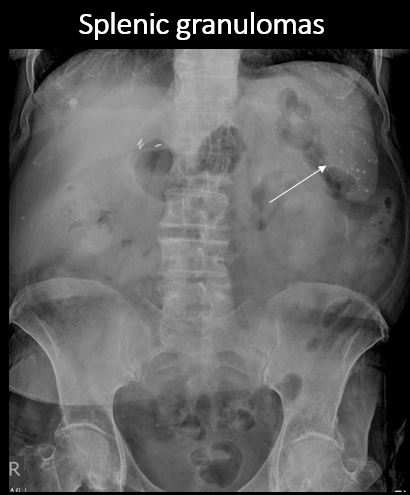

There are splenic associated calcifications. [Yes/No]

There are dystrophic or additional intra-abdominal soft tissue calcifications. [Yes/No]